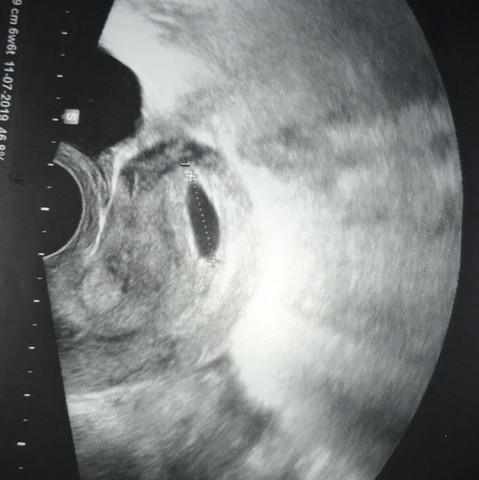

6 Woche Schwanger Ultraschall

6 woche schwanger ultraschall. Die meisten Frauen suchen etwa zwischen der 6 und 8 Schwangerschaftswoche (8 SSW) den Frauenarzt auf, um die Schwangerschaft bestätigen zu lassen Wenn Sie möchten, kann Ihr Partner zu dem Termin mitkommen. Sie ist in einer Woche von 6mm auf 11mm gewachsenLeider kann man aber keine "Babyumrisse" sehen Mein HCG Wert hat sich von 400 auf über 4000 erhöht, allerdings ist mein Progesteronwert gesunken Mein Arzt meint nun, dass ich vielleicht noch gar nicht in der 6 SSW bin, dass kann aber nicht sein, weil wir danach keinen Verkehr mehr hatten. Das allererste Zeichen einer intrauterinen Schwangerschaft, das wir im Ultraschall erkennen, ist die meist kreisrunde, echoarme Struktur, die im Ultraschalljargon „Fruchtsack“ genannt wird Der Fruchtsack entsteht zwar durch den Embryo, er ist genau genommen ein vom mütterlichen Endometrium gebildetes „Drumherum“, in dem sich die.

6 Schwangerschaftswoche In der sechsten Schwangerschaftswoche ist der Embryo etwa drei bis sechs Millimeter langUnd auch wenn seine Erscheinung noch stark an eine Kaulquappe erinnert wichtige innere Organe wie Herz, Nieren, Leber und Magen bilden sich bereits aus, Kopf und Rumpf nehmen Form an und das Neuralrohr, die Verbindung von Gehirn und Rückenmark, schließt sich. Ab der 6 Schwangerschaftswoche können bei einer Ultraschalluntersuchung die ersten Herzschläge erkannt werden Das Blut des Embryos zirkuliert und ist daher blinkend zu erkennen In diesem frühen Stadium der Schwangerschaft können sich die Warzenhöfe dunkel verfärben Intensität und Ausprägung sind dabei von Frau zu Frau verschieden. Hier unser erstes Video der wöchentlichen Schwangerschaftsupdates zu Woche 11 Hier erfahrt ihr alle Neuigkeiten rund um die Schwangerschaft und diesmal gibt.

Eine Woche später ist der Dottersack zu sehen Die Fruchthöhle ist jetzt ca 10 mm groß Bild 2 Wenn die Fruchthöhle 1 cm groß ist oder man sicher sein kann, dass die 6 SSW begonnen hat, sollte der Dottersack (roter Pfeil) zu sehen sein Es sind wieder nur einige e und das Kind erscheint im UltraschallBild. Erfahre jetzt, wie hoch der hCGWert für jeden einzelnen der Schwangerschaft sein soll Mit unserer hCGTabelle erhälst Du alle wichtigen hCGWerte für Blut und Urin Wir verraten Dir außerdem, welche Schwangerschaftstests sensitiv genug sind, um frühzeitig hCG nachweisen zu können. 11 Schwangerschaftswoche Alles zur Größe des Babys und Entwicklung in Ihrem Bauch, Anzeichen, Gewichtszunahme und Untersuchungen wie Ultraschall.

Antwort Eine Schwangerschaft kann dann sicher nachgewiesen werden, wenn in der Gebärmutter eine Fruchthöhle mit einen Embryo oder einer Struktur, die zu der Fruchtanlage gehört (Dottersack), zu sehen ist Das ist mit guten UltraschallGeräten etwa ab der 5 bis 6 Schwangerschaftswoche möglich, also ab einer Woche nach Ausbleiben der Regel. Ein sicherer Nachweis der Schwangerschaft über Ultraschall ist aber erst ab der sechsten Schwangerschaftswoche möglich Trotzdem ist auch jetzt schon etwas im Ultraschall zu auszumachen Der Embryo sieht auf dem Bild wie ein Punkt aus, der etwa die Größe eines Stecknadelkopfs hat 6 Woche 4 Woche Zurück zur Übersicht Diese Artikel. Was bedeutet 6 SSW?.

In der 6SSW ist eine rasante Entwicklung des Babys im Bauch der Mutter zu erkennen, die sich in zunehmenden Schwangerschaftssymptomen äußert Nachdem in der 5SSW das Herz zu schlagen begonnen hat, nimmt nun in der 6 SSW auch die Größe des Babys an Volumen zu, das Gehirn entwickelt sich weiter und die Gliedmaßen und Organe nehmen mehr Form an, was zum Teil auch im Ultraschall sichtbar wird. Bei jedem Wurf bringen Katzen zwischen 6 und 8 Kätzchen zur Welt Das ist ebenfalls von der Rasse und anderen Faktoren abhängig Während der Schwangerschaft nehmen Katzen zwischen 1 und 2 Kilo an Gewicht zu Nach ca 40 en kann per Ultraschall beim Tierarzt herausgefunden werden, wie viele Kätzchen es werden. Hallo, Habe letzte Woche Montag einen Schwangerschaftstest gemacht dieser war nur ganz leicht Positiv lautlachen Da ich mir nicht sicher war bin.